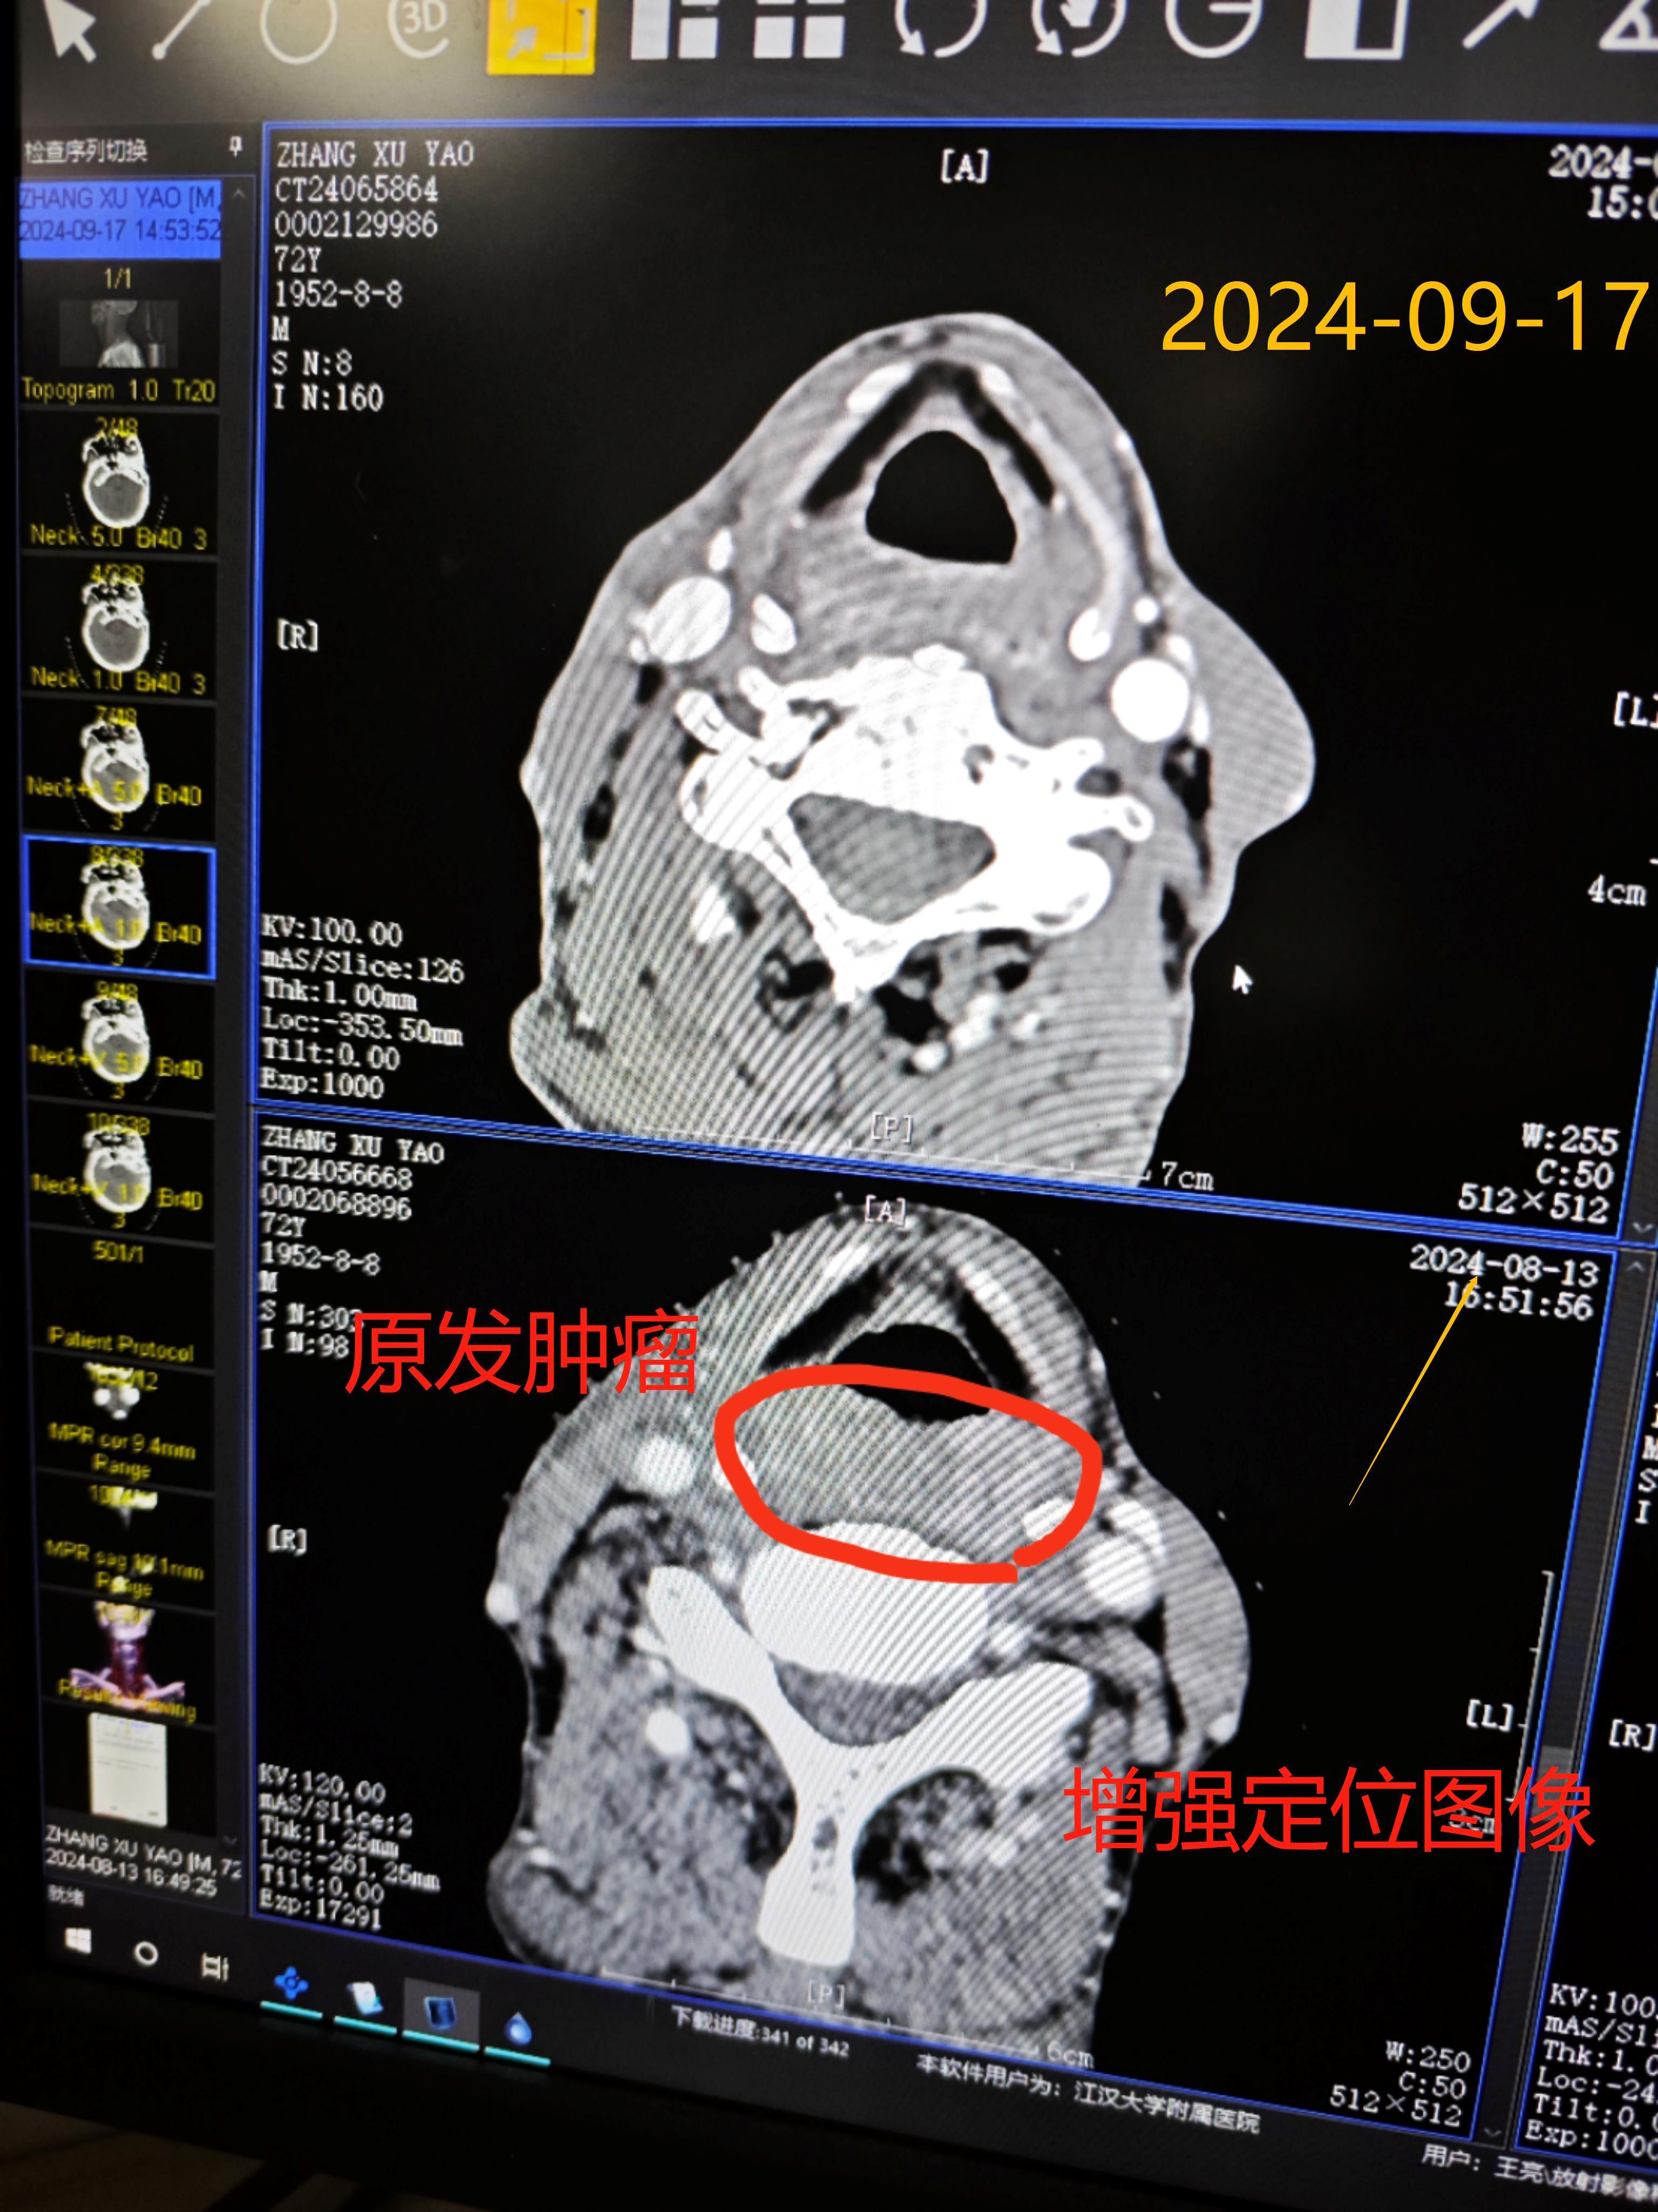

下咽癌以局部治疗为先导的综合治疗

图片尺寸3072x4096

图片尺寸3072x4098